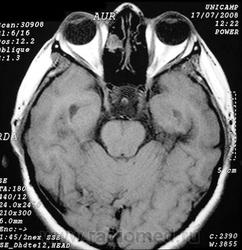

Фронтоэтмоидальное энцефалоцеле.

Отдел патологии, школа медицинских наук.

Государственного Университета Кампинас (UNICAMP).

Кампинас, Сан-Паулу, Бразилия.